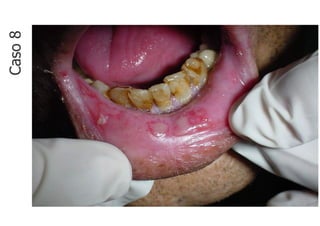

Caso

8

• Lesão fundamental: úlcera

• Localização: mucosa labial inferior

• Quantidade: múltiplas

• Tamanho da maior: 5,0 x 5,0 mm

• Borda: bem delimitada

• Cor: branca

• Base: séssil

• Aspecto superficial: lisa

• Em mucosa labial inferior nota-se múltiplas

ulcerações dolorosas, recobertas por pseudo-

membrana esbranquiçada, bem delimitadas, com

base séssil, superfície lisa e que medem

aproximadamente a maior 5,0 x 5,0 mm em seus

maiores diâmetros.

CASO 8 - Descrição